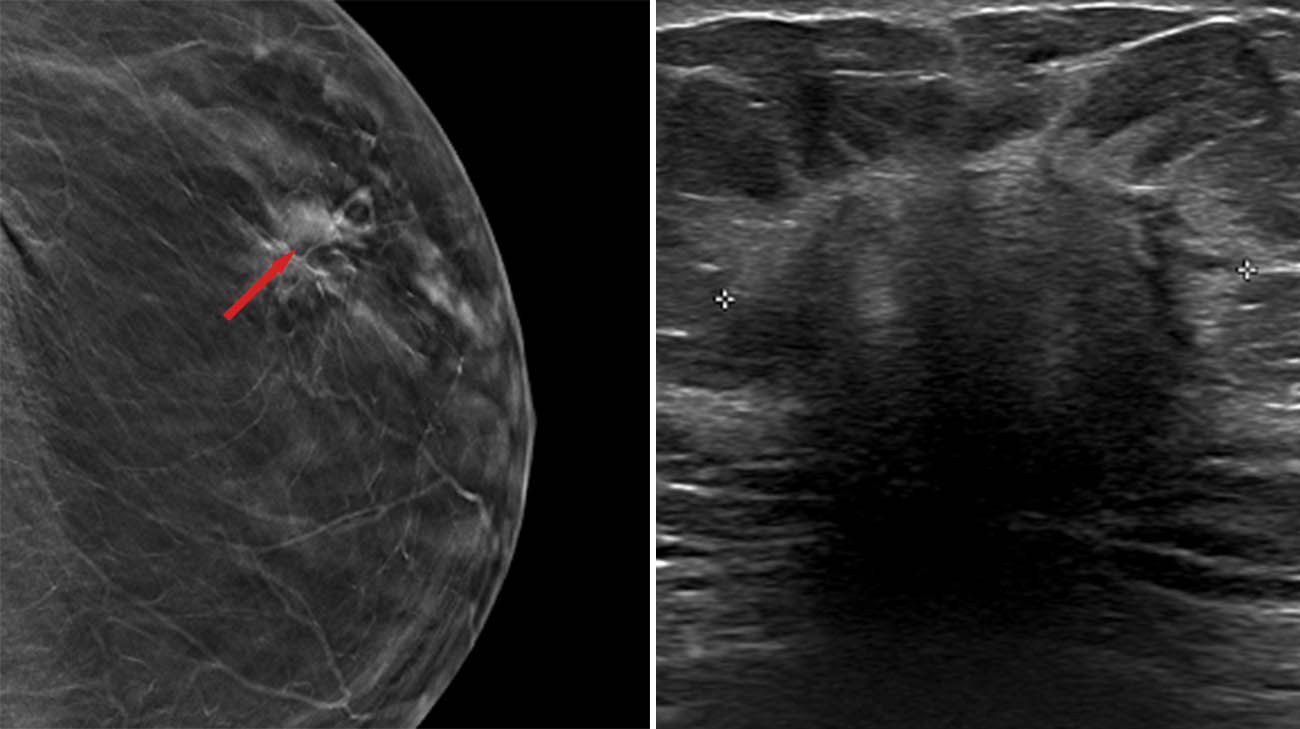

“The X-rays showed a worrisome mass on the left breast, about three centimeters large,” says Dr. Fenton, executive medical director of the McDowell Cancer Center and the Breast Health Center. “That’s bigger than we would like to find but still treatable. I was also worried about an enlarged lymph node under her left arm,” which could indicate the cancer had spread.

Virgie's mammogram (left) and ultrasound (right) showing the cancerous mass. (Courtesy: Cleveland Clinic)

Fortunately, the lymph node did not reveal signs of cancer, and Virgie’s cancer was in stage 1. “She’s very lucky,” notes Dr. Fenton. “The thing about invasive lobular is that it can either behave nicely, and stay put, or it can spread more diffusely to the surrounding tissue. Hers stayed put.”